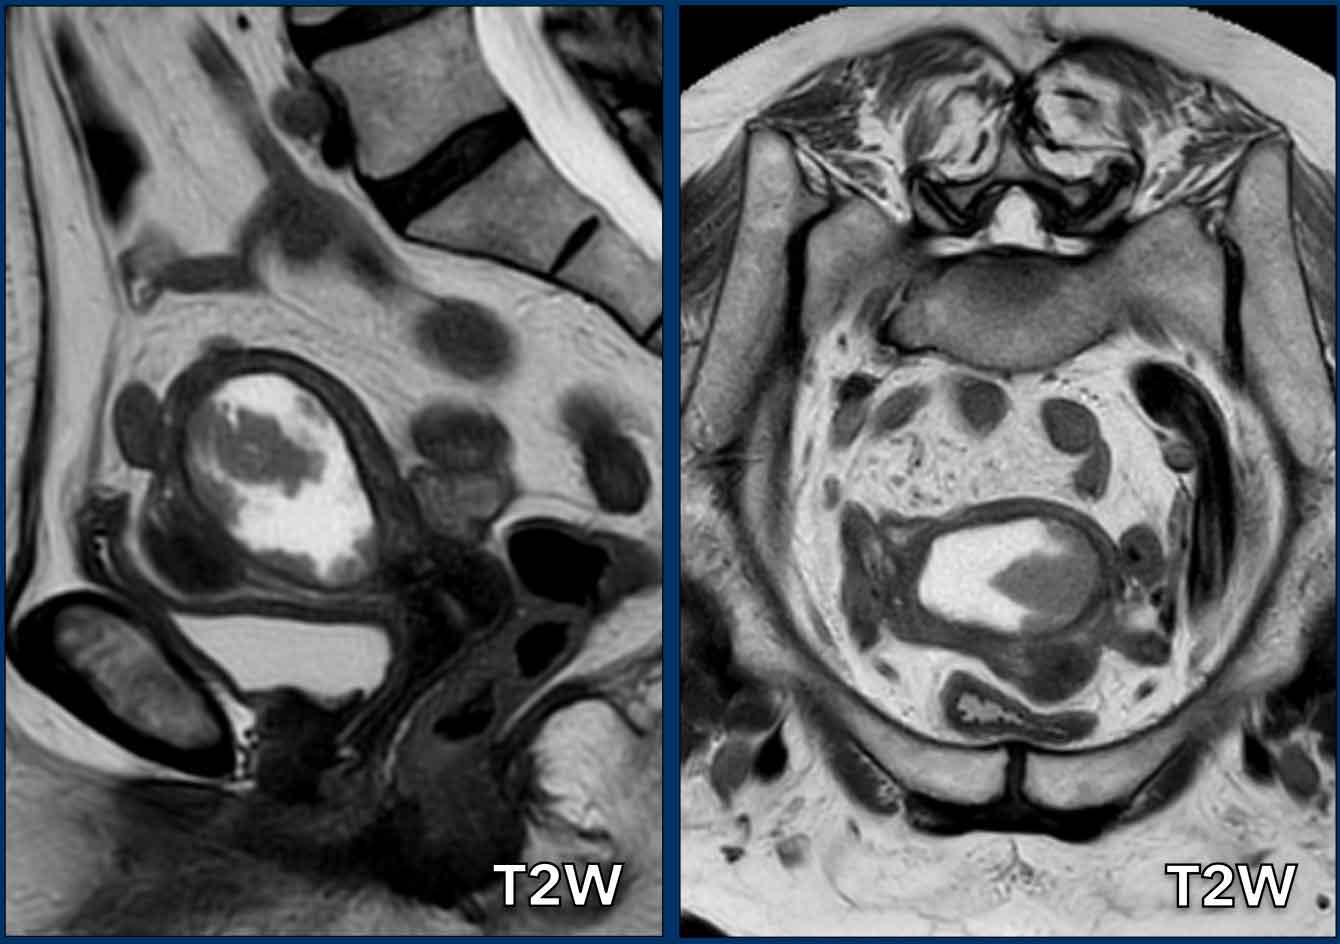

Lợi ích của DWI

Đôi khi khối u khó xác định ranh giới trên chuỗi xung T2W do gần như đồng tín hiệu so với cơ tử cung.

Trong những trường hợp như vậy, DWI giúp phân biệt giữa khối u và cơ tử cung.

Hình ảnh

Trên chuỗi xung T2W, khối u gần như đồng tín hiệu với cơ tử cung.

Chuỗi xung DWI cho thấy có xâm lấn cơ tử cung nhưng dưới 50%.